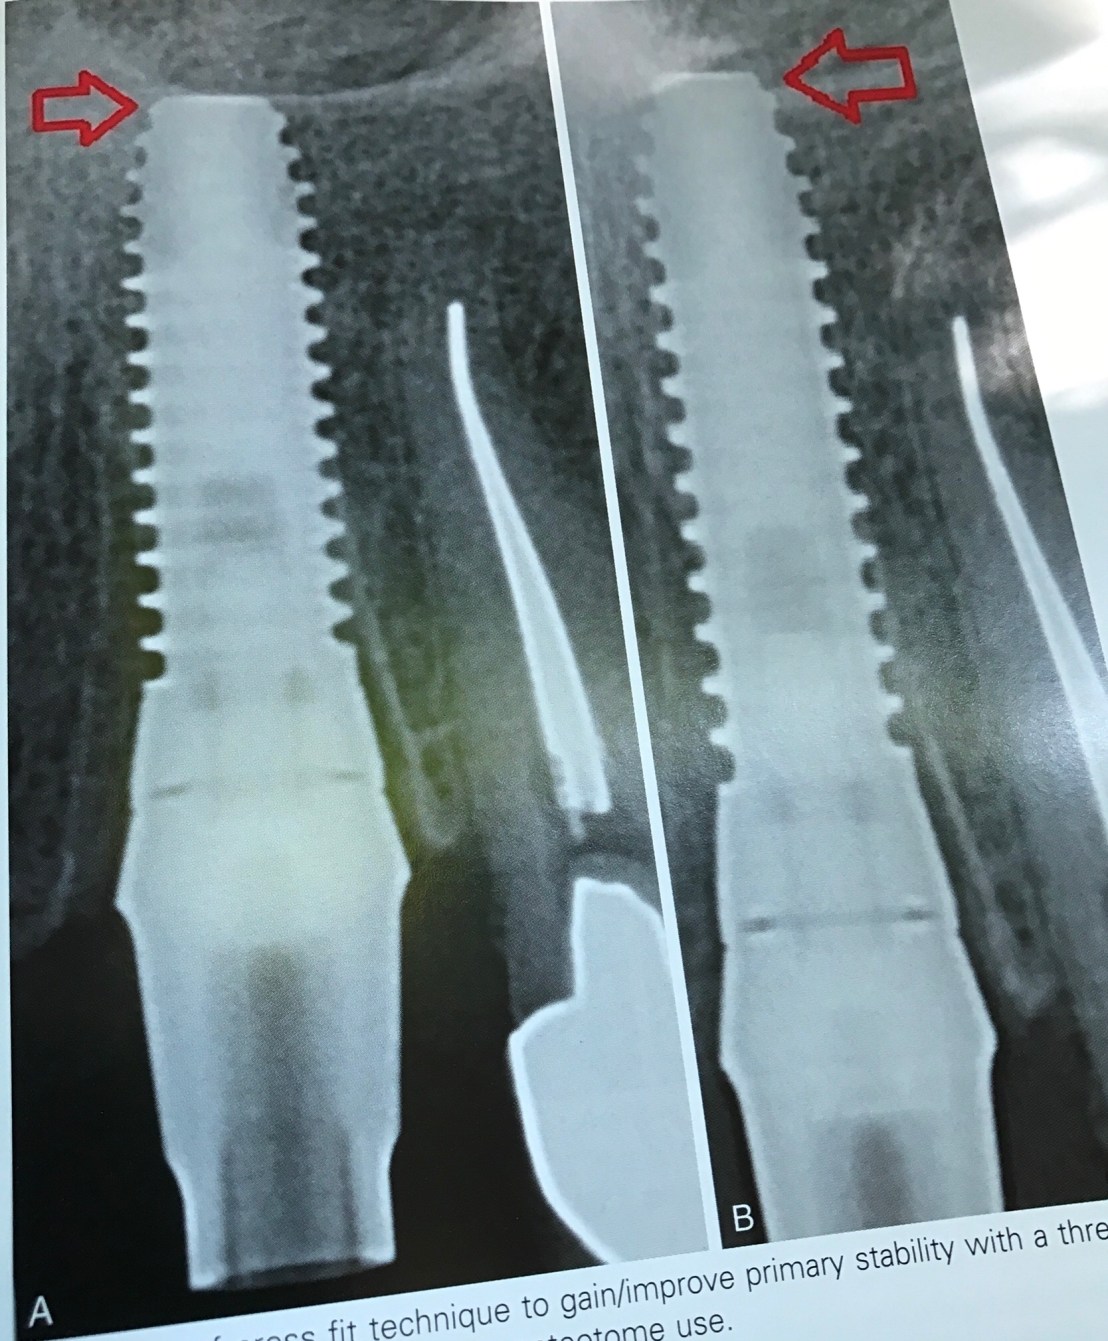

Film แสดงการวางตำแหน่ง Implant ที่ลึก (เทียบระดับ CEJ) และปลายที่รบกวน Mand canal

ถ้ามอง Cross section view ในรูป B รูเปิดที่เห็นด้าน buccal นั่นคือ Mental foramen ครับ

รูป E ภาพ CBCT แสดงการยืนยันชัดเจน

แสดงการ Gain Primary stability โดยการใช้ Osteotome (รูป B คือหลังใช้ Osteotome)

แสดงความผิดพลาดในการวางตำแหน่ง จะเห็นได้ว่า แม้จะมี socket ถอนฟันเป็นตัว guide แต่ตำแหน่งที่ฝังยังออกไป Distal มาก

ดังนั้นการใช้ข้อมูลจาก X-ray + Surgical stent จึงยังเป็นสิ่งจำเป็นอยู่ แม้ในเคส Immediate ก็ตาม